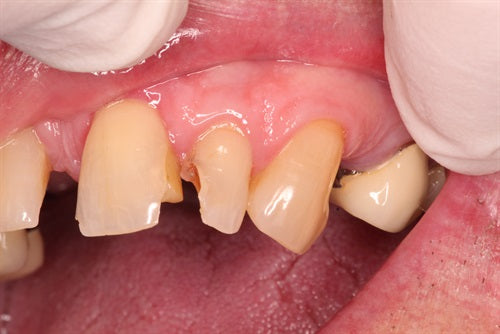

Extremely difficult lower anteriors

Posted on June 13 2022

Introduction: This case was completed by Dr. Sunny (@smilesbysunny) from the UK. He offers one day courses (@drecomposite) in the UK covering the Greater Curve technique. Dr. Sunny acknowledges he can... Read More